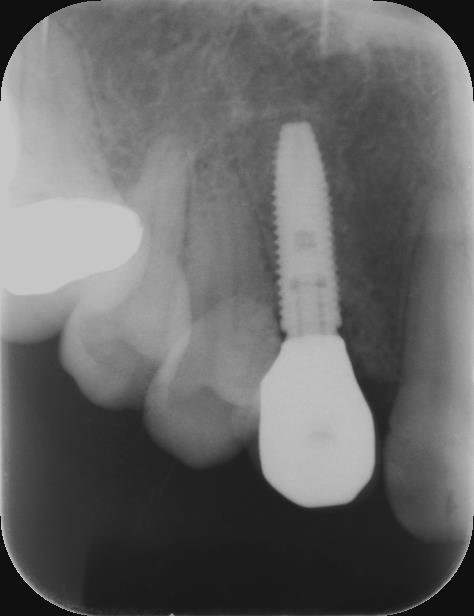

術前レントゲン

術後レントゲン

| 主訴 | 折れている歯を眠っている間に完全無痛でインプラントをして欲しい。インプラント手術自体をいかに痛みや不安がなく治療ができる医院がないかを探していた。抜歯と同日のインプラント手術を「完璧にできる」という歯科医師に治療してもらいたいと思っている。 |

|---|---|

| 年代・性別 | 60代 男性 |

| 治療部位 | 左下7 |

| 治療費用 | インプラント手術料 300,000円 |

| 手術回数 | 2回 |

| 治療期間 | 4ヶ月 |

| 手術時間 | 90分 |

| 治療回数 | 5回 |